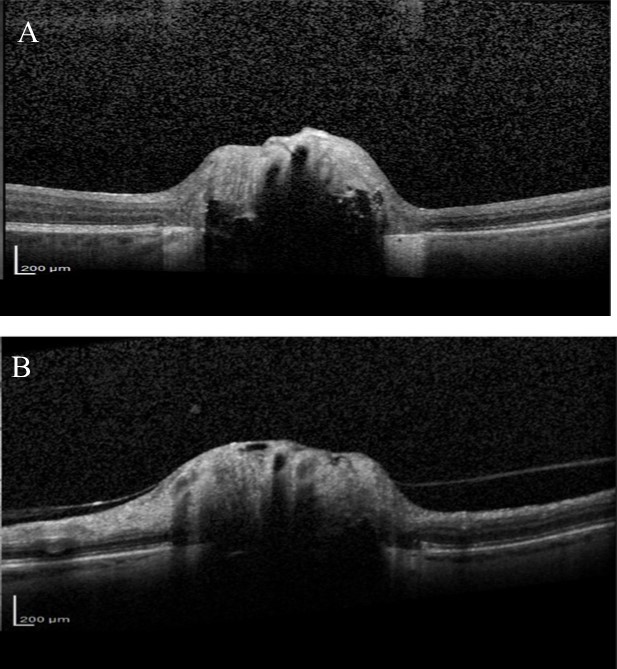

Over the next 6 months she felt the deterioration in vision in right eye had stabilised but complained that the vision in her left eye was gradually worsening. Visual acuity remained good but visual field testing confirmed a deterioration showing there had been a marked decline in the left eye visual field with MD deterioration from -9.59 to -24.01(Figure 4). Blood tests were taken for common Leber’s hereditary optic neuropathy mutations, which were negative. Vitamin B12 and folate levels were within normal range. Fundus fluorescein angiography (FFA) was also performed, looking for possible associated anterior ischaemic optic neuropathy (AION), but no evidence of late leakage was found. OCT examination of the RNFL was also performed and showed significant thinning in both eyes (Figure 5). Average RNFL thickness was only 57 um in the right eye but measured 87 um in the left, although the inferotemporal sector was outside normal limits in the left eye. Enhanced depth imaging (EDI) OCT was also performed to better ascertain the location and extent of the ONHD (Figure 6). Electro-diagnostic tests showed reduced amplitudes and prolonged latency on the visual evoked potential (VEP) for both eyes, with a normal electroretinogram. The reduced amplitude and prolonged latency on the VEP was suggestive of a non-demyelinating optic neuropathy.

Most previous cases of rapid visual loss in ONHD have been associated with an acute vascular event or choroidal neovascualarization. We performed FFA to investigate for secondary causes of visual loss and to look for disc leakage, however FFA was normal. Reduced amplitude and prolonged latency on the VEP, with a normal electroretinogram, suggested visual loss was due to an optic neuropathy. This is in agreement with previous studies, which have shown patients with ONHD to have prolonged latency on VEPs18, 19, 20, a finding consistent with a mechanical compressive mechanism of axonal damage. The prolonged latency and reduced amplitude in our patient was likely due to the marked extent of the nerve damage 21. Although our patient had marked ONHD, as evident from the EDI-OCT, B scan ultrasonography and autofluorescence, it is not possible to be certain that ONHD was the sole cause of visual deterioration. It is conceivable that she also had coexisting normal tension glaucoma, however the rapid deterioration in visual field would not be characteristic of this condition. Given the difficulty of diagnosing glaucoma in patients with ONHD, and the possible increased risk of IOP-mediated RGC injury in an already compromised eye, we opted to treat our patient with topical IOP lowering medication7,22.

Improvements in technologies such as EDI-OCT and Swept Source OCT might enable better identification of glaucomatous changes in eyes with ONHD as they allow imaging of deep ocular structures13,24,25. The ability of EDI-OCT to image structures 500-800 um deeper than conventional OCT allows the posterior limit of the drusen to be imaged13. Several studies have recently shown that using EDI-OCT or Swept Source OCT it is possible to visualise the extent of ONHD and to examine the thickness of neighbouring neural tissue13. Our patient had marked RNFL loss on SDOCT, particularly in the right eye. The RNFL thickness was outside normal limits, however, normative databases should be interpreted with caution in eyes with ONHD particularly as the risk of segmentation errors is likely to be higher due to abnormal anatomy. Although glaucomatous RNFL thinning characteristically involves the inferior-temporal and superior-temporal circumpapillary RNFL, the pattern of RNFL loss may not help differentiate whether this is related to ONHD or glaucoma as the location of RNFL defects associated with ONHD is likely to vary depending on location of the ONHD.